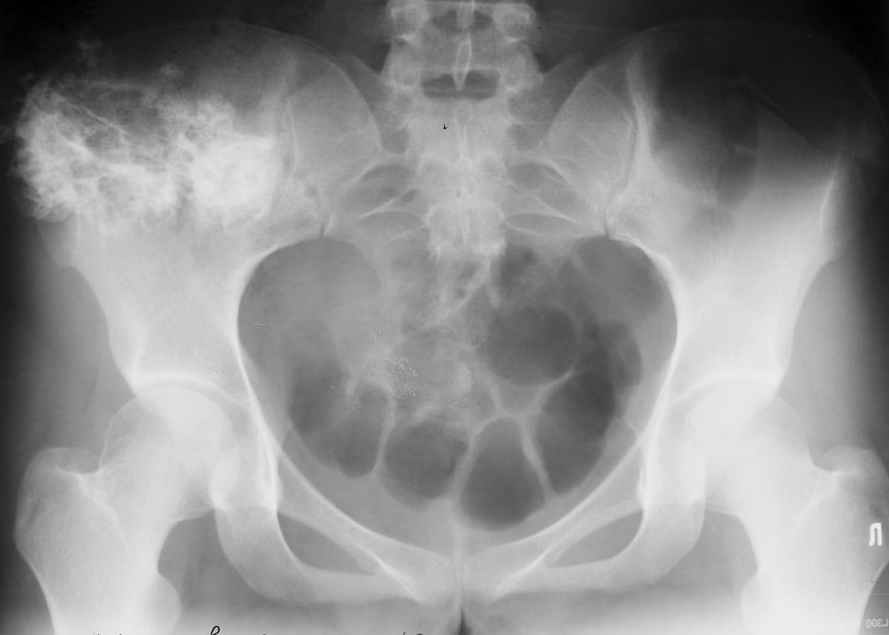

Остеохондрома подвздошной кости